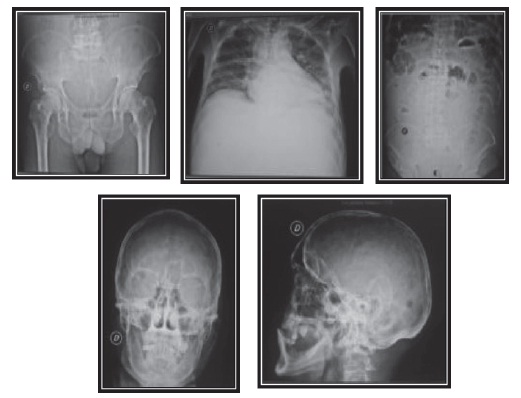

La analítica muestra: leucopenia 2.660, hemoglobina del 4,9 %, hematocrito al 14,4 %, plaquetas 58 000 mm3, glucosa 85 mg, urea 52 mg, creatinina 2 mg, proteínas totales 11,4 g/dl, albúmina 2,3 g/dl, globulina 9,10 g/dl, bilirrubina total 0,36, dhl 64 U/l, tgo 30 U/l, tgp 11 U/l, examen de orina patológico, inr: 3,15, ecografía abdominal: cirrosis hepática con ascitis, endoscopia alta normal, estudio de líquido ascítico pap (-), block cell (-), bk (-), gram y cultivo (-), adenosina de amina (-), calcio sérico 8,8, vsg: 84 mm/h, proteinuria en orina de 24 horas 0,38 g/24 h, proteína de Bence-Jones negativo. El resultado de la prueba β2-microglobulina sérica se muestra elevada (6.0 mg/l). Al rastreo óseo de pelvis, abdomen, tórax y cráneo, se observan lesiones de tipo sacabocados (figura 1), por lo que se realiza biopsia de hueso con resultado de plasmocitoma (figura 2).

El mieloma múltiple es una enfermedad de predominio en mayores de 50 años, pero también se puede presentar raramente en las primeras cuatro décadas de vida. Respecto al paciente de 49 años con antecedente de alcoholismo crónico de más de 20 años y con un cuadro de falla renal aguda, trastorno hematológico y síndrome ascítico, se sospecha rápidamente un cuadro cirrótico descompensado; pero, por el antecedente importante de presentar dolor óseo, más hospitalizaciones anteriores con el cuadro de dolor y observar la inversión albúmina-globulina marcada, se planteó la posibilidad de una gammapatía monoclonal, que, asociada con el estudio de imágenes donde se evidencian lesiones líticas en cráneo, pelvis, columna (figura 1), y vsg incrementado, orientó al diagnóstico de mieloma múltiple en paciente con cirrosis hepática. Por tal motivo, se efectuaron los exámenes específicos respectivos: biopsia de hueso, dosaje de inmunoglobulinas, proteinograma electroforético, β2-microglobulina, proteína de Bence-Jones. Así mismo, se pensó en una neoplasia cuando el valor de las alfa-2 globulinas, sumado al de las betaglobulinas, fue superior al doble del de la gammaglobulina. Con los anteriores criterios mencionados, se concluyó que el diagnóstico definitivo era mieloma múltiple IgA EC IIIB + cirrosis hepática.